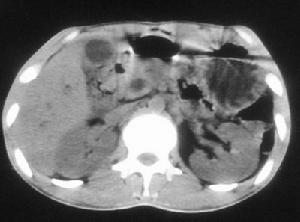

膽囊造影和B型超聲肝膽掃描是診斷慢性膽囊炎很有價值的檢查方法。膽囊造影可以發現膽結石、膽囊縮小變形,以及濃縮和收縮不良等情況,有時膽囊不顯影。B超檢查除了可探查出膽結石和膽囊外型改變以外,還能看到膽囊壁有變毛糙、增厚等徵象。有上述症狀的病人,應及時就醫,通過以上檢查,一般可以明確慢性膽囊炎的診斷。

急性發作時與急性膽囊炎的實驗室檢查相同,無急性發作時可無異常改變。B超檢查可探知膽囊的大小、壁厚薄、有無結石等。口服膽囊造影檢查可觀察膽囊收縮功能是否存在、膽囊內有無結石等。